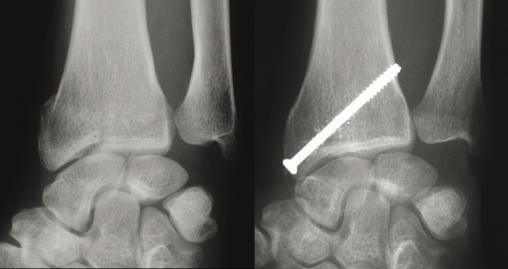

© Guillaume Herzberg, La Revue du Praticien (À gauche) Fracture marginale externe détachant un gros fragment de styloïde radiale.(À droite) Traitement : brochage percutané ou sous contrôle arhtroscopique.